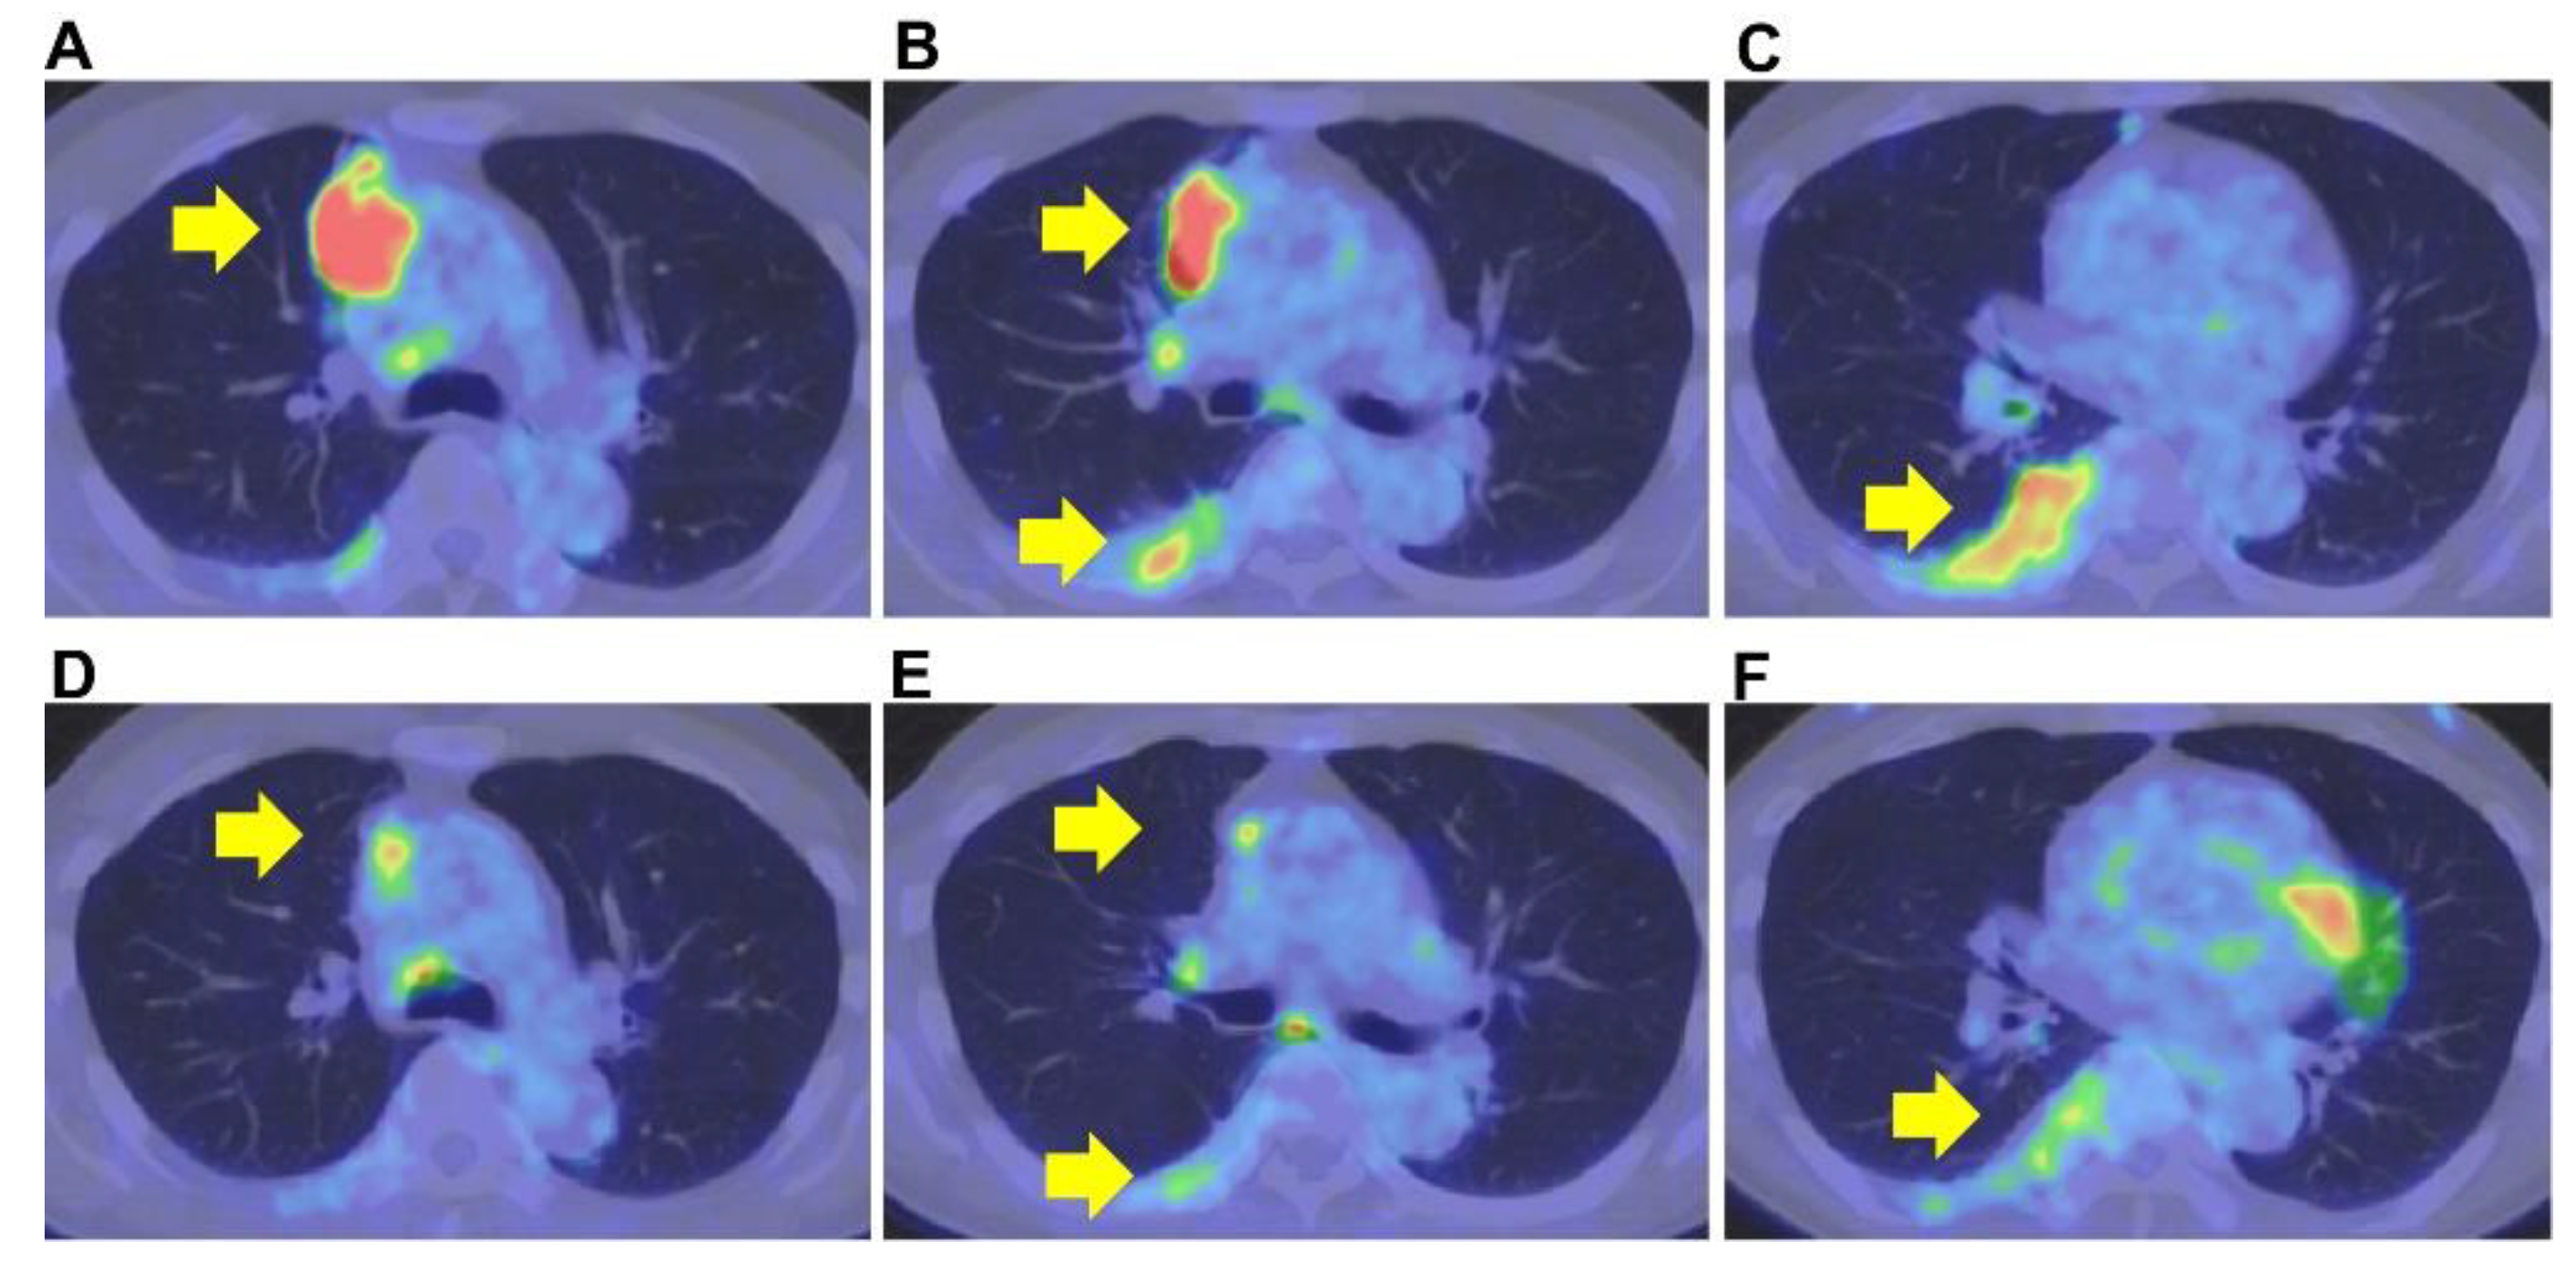

The primary lesion was located between the mediastinum and the right lung lobe, thus, it was difficult to distinguish whether the tumor originated from the mediastinum or the lungs. A thin bronchoscope with endobronchial ultrasonography and a guide sheath was inserted into the right B3biαx bronchial branch, and a biopsy within the tumor was performed. However, the histopathological study showed no diagnostic findings. CT-guided needle biopsy (CTNB) was then performed (Figure 2A,B). An expert pathologist revised the tissue specimen sampled by CTNB. The pathology report revealed a solid tumor with malignant squamous cells and scarring tissue and positive immunostaining for p40 and CK5/6. The pathological diagnosis was non-keratinized squamous cell carcinoma (Figure 3A–D). The differential diagnosis between thymic carcinoma and primary lung cancer was difficult based on imaging and histopathological findings. A PET/CT scan showed a primary tumor with high 18F-fluorodeoxyglucose accumulation, a maximum standardized uptake value of 10.95, and multiple nodules with a maximum standardized uptake value of 7.08 in the right lung interlobar region and pleura. The diagnosis was cancerous pleural dissemination (Figure 4A–F). The tumor was negative for epidermal growth factor receptor (EGFR) gene mutation, anaplastic lymphoma kinase (ALK) fusion gene, and the proto-oncogene tyrosine-protein kinase (ROS1). The degree of tumor PD-L1 (22C3) staining was low (5–10%). The tumor was considered unresectable.

Figure 4.

Positron emission tomography–computed tomography. Before therapy, the primary tumor’s positron emission tomography–computed tomography showed high 18F-fluorodeoxyglucose accumulation and a maximum standardized uptake value of 10.95 (A–C). After therapy, the primary tumor’s positron emission tomography–computed tomography showed a maximum standardized uptake value of 4.5 (D–F).

CT scan showed tumor size reduction (partial response) after two cycles of combination therapy at the outpatient department, and a CT scan performed after four additional cycles of combination therapy showed no deterioration. Therefore, therapy was changed to maintenance therapy with pembrolizumab. The tumor size was gradually reduced following maintenance therapy with pembrolizumab (Figure 5). A PET/CT scan performed after twelve pembrolizumab cycles showed substantial tumor size reduction with decreased standardized uptake values (Figure 4). Maintenance therapy was continued for up to sixteen cycles due to a good response to the therapy and the patient’s stable performance status. Fourteen months after starting the therapy, the patient had a twelve-month exacerbation-free period. After that, the patient had an exacerbation of his disease that was treated with a combination of cisplatin, doxorubicin, cyclophosphamide, and vincristine as a second-line therapy and subsequently with amrubicin as third-line therapy. Due to the patient’s strong desire, pembrolizumab was re-administered as a fourth-line therapy, although no response was observed. Therapy with lenvatinib was then indicated, and the clinical response was good. Lenvatinib is an oral multi-target kinase inhibitor. The use of lenvatinib was associated with a good response rate (38%) in thymic carcinoma after platinum-based chemotherapy [11]. In the current case, lenvatinib was administered as fifth-line therapy without any PS impairment. Good tumor response is expected with the ongoing Phase 2 trials with pembrolizumab and lenvatinib for B3 thymoma or thymic carcinoma after platinum-based chemotherapy (PECATI study) [12]. In addition, platin-based chemotherapy combined with pembrolizumab (NCT04554524) as first-line therapy for patients with thymoma and thymic carcinoma is also currently underway (https://clinicaltrials.gov/ct2/show/NCT04554524 accessed on 7 July 2022).